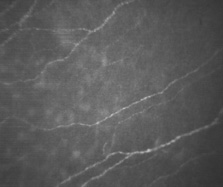

As the midstromal fibers travel toward the central cornea, axons become finer, and beaded features are seen along the filaments prior to their termination. Collaterals from the midstromal fibers branch anteriorly at 90 degrees to create an extensive sub-Bowman's layer plexus. Fibers from the plexus travel anteriorly through Bowman's layer toward the epithelium, where they again turn at 90 degrees and travel parallel to the corneal surface just posterior to the epithelium. Based on confocal microscopy, the majority of fibers in the subbasal plexus of the central cornea appear to be oriented along the superior-inferior axis. There are approximately 5400 to 7200 nerve bundles in the subbasal plexus; because each bundle may contain several axons, the total number of axonal fibers may be as high as 44,000.105 Each fiber immediately forms numerous, elaborate leashes with up to several dozen beaded axon terminals per leash and some additional unbeaded fibers. The beaded appearance was at one time considered an artifact of tissue processing or trauma; however, confocal microscopy has shown these to be genuine features (Fig. 24). The unbeaded straight terminals are not seen entering the epithelium; however, the beaded terminals of the leashes diverge vertically and obliquely among the epithelial cells in a complex manner before terminating at the level of the apical cells (Fig. 25).102 The diameter of the individual nerve fibers in the subbasal plexus are between 0.05 and 2.5 μm with most being in the range of 0.1 to 0.5 μm.

Fig. 24. Confocal microscopic transverse image of the human basement epithelial membrane in vivo demonstrates unmyelinated beaded nerve leashes. These send off nerve terminals within the corneal epithelium (500×; courtesy of Nidek Technologies).